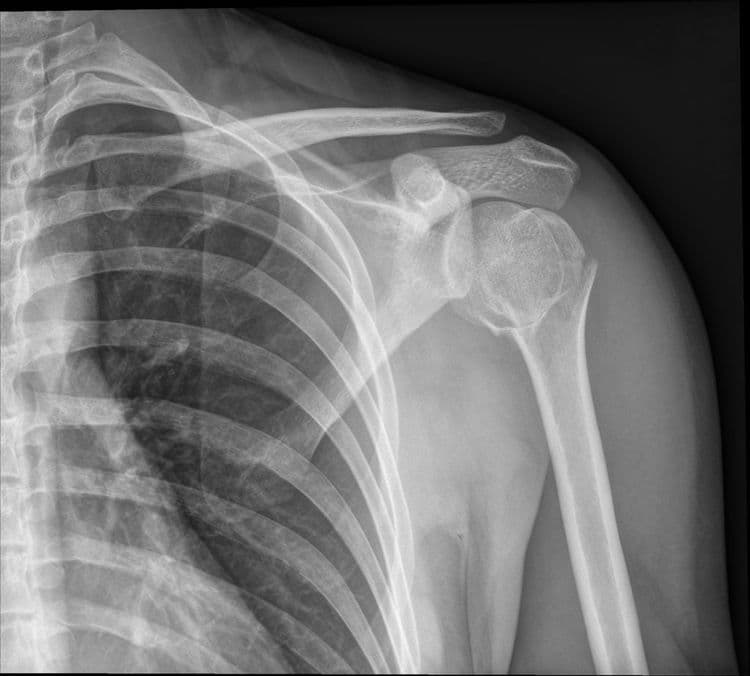

Hairline Fracture - अतिशय बारीक फ्रॅक्चर जे कधी कधी एक्स रे मधून दिसत नाही.

Impacted Fracture - एखादे हाड तुटते तेव्हा त्या हाडाचा हिस्सा दुसऱ्या हाडांमध्ये घुसण्याची स्थिती.

IntraArticular Fracture - हाडासोबतच सांध्याचा पृष्ठभाग सुद्धा फ्रॅक्चर होणे.